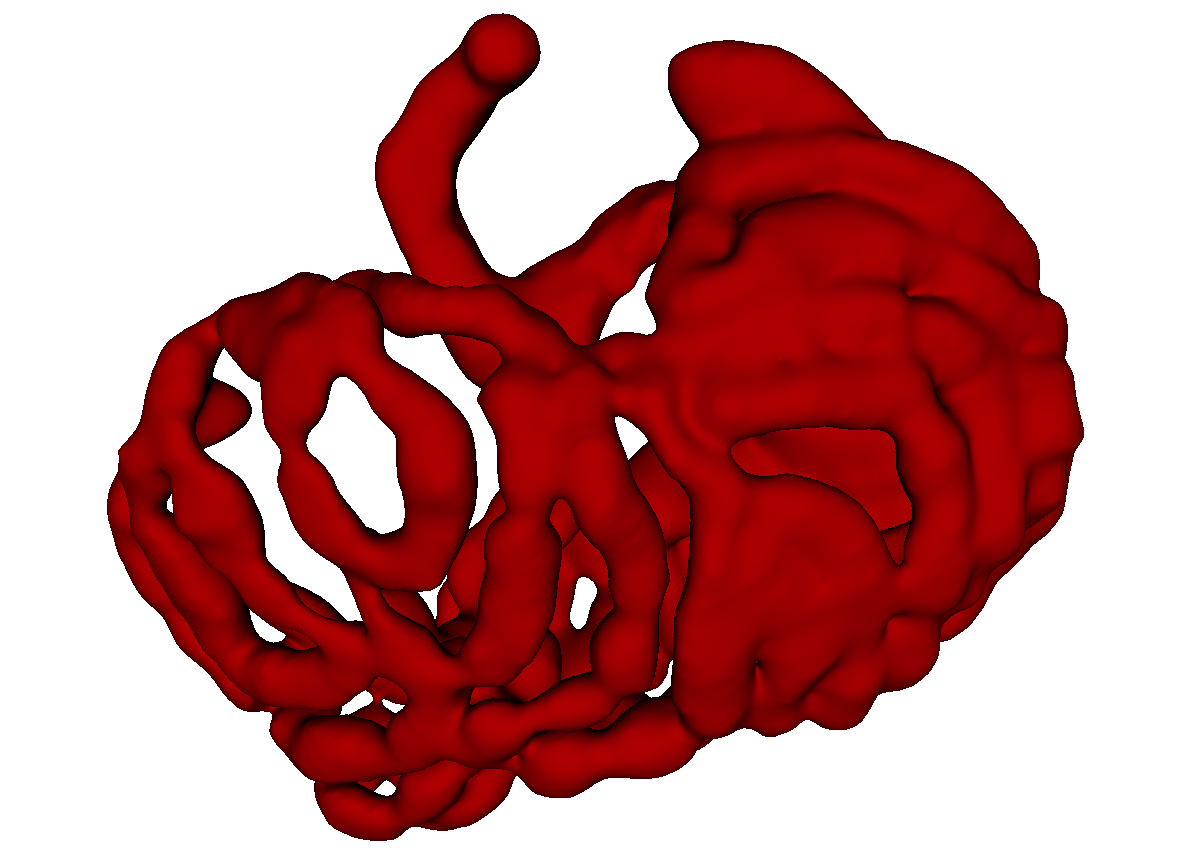

Fig. 3 shows example segmentation results. The proposed method eliminates false positives on the large bowel by the help of the applied topological constraint. Fig. 4 further clarifies the effectiveness of the proposed method by presenting 3D rendered segmentations. The proposed method produces a more topologically correct segmentation of the small bowel with fewer false positives. Fig. 5 presents example barcode diagrams, which again show the reduced numbers of connected components and holes within the segmentation result of the proposed method.

A

B

C

D